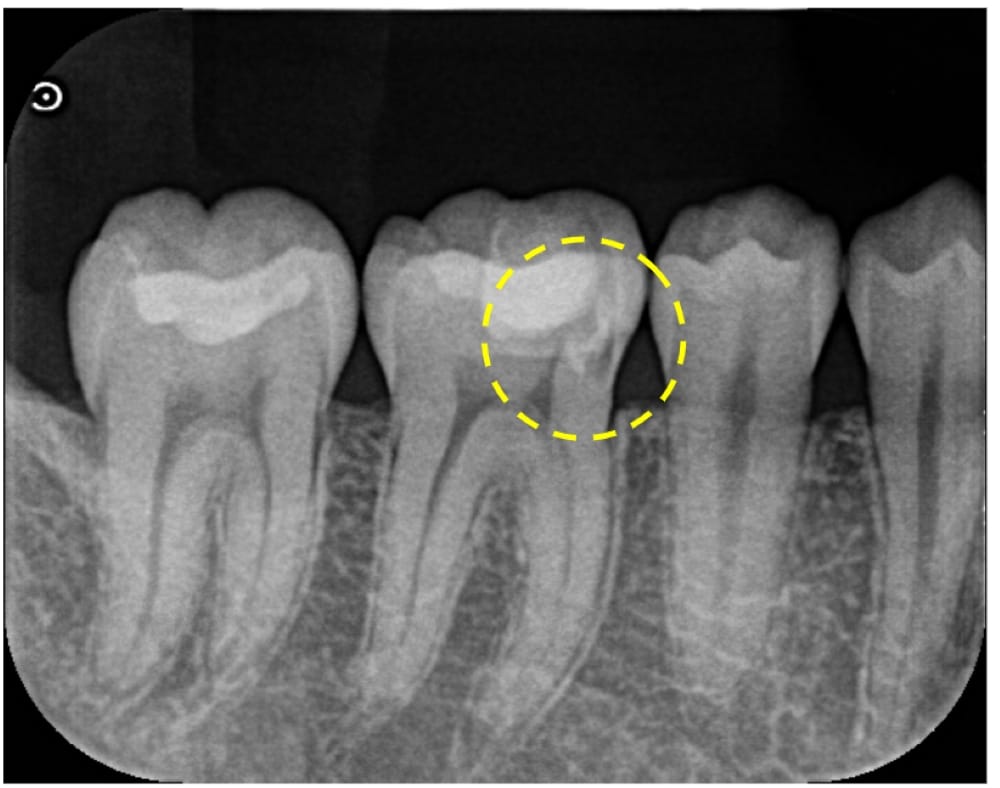

虫歯が深く神経を取らないといけないと言われたが残せるなら残したい【30代男性】大きな虫歯に対する歯髄保存療法_症例49